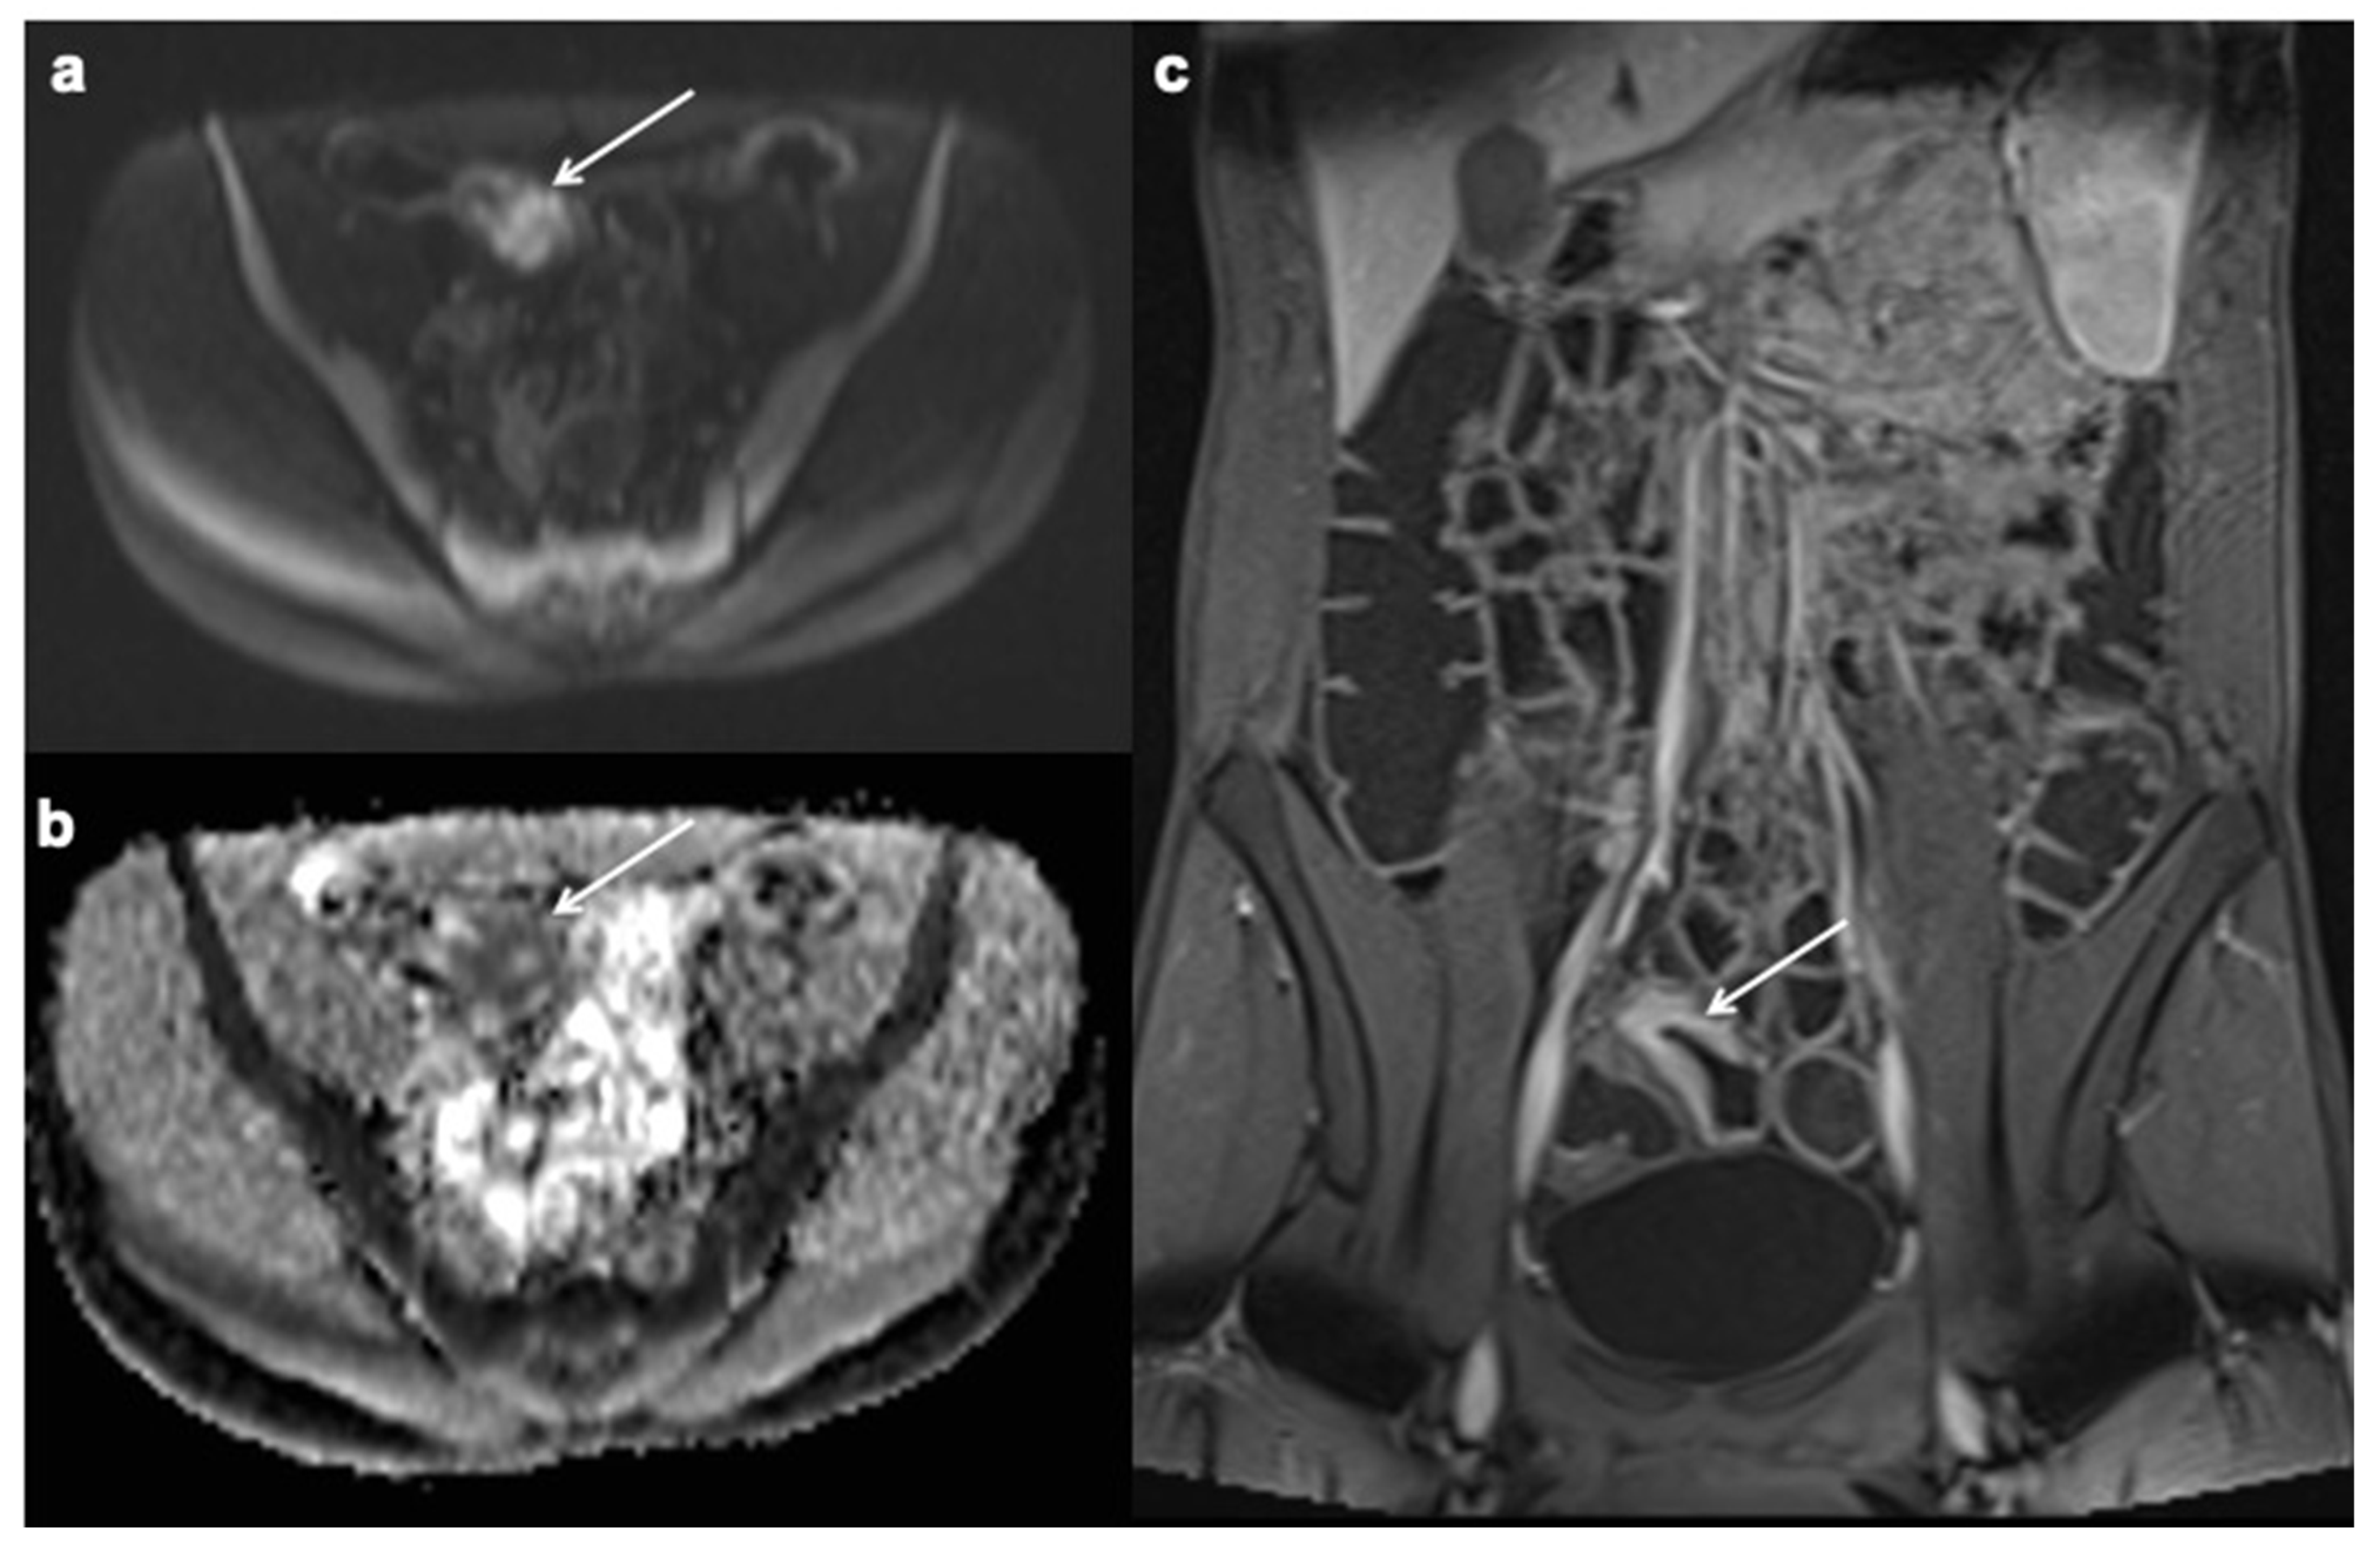

10. Imaging Findings Associated with Active CD Inflammation

11. Imaging Findings Associated with Penetrating CD Inflammation and Complications